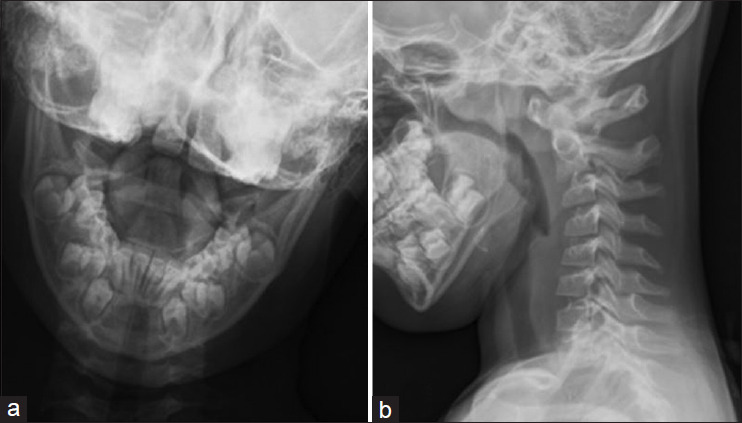

Atlanto-axial rotary subluxation (AARS) is rare but recognized as a significant cervical spine injury following a fall or physical impact on the head or neck in children aged 5-15 years. Trampoline use has been increasing among children, as have the trampoline-related injuries (TRI). We present a case series of AARS following trampoline injuries, highlighting clinical presentation, diagnosis, and management, especially in an emergency setting. We report four children with an average age of 8.5 years (range 6-12 years) presented to our hospital emergency service with neck pain and torticollis following a TRI. The diagnosis was confirmed through X-ray and computed tomography imaging, revealing Fielding and Hawkins type 1 AARS. Conservative treatment with analgesics, muscle relaxants, and a cervical collar led to recovery in three cases, while one required halter cervical traction for persistent deformity. All patients recovered completely, with no long-term complications. AARS in children is largely a type 1 injury with a favorable prognosis. Early recognition and management are crucial in preventing complications. The increasing incidence of neck injuries caused by trampoline use in children necessitates strict safety regulations regarding its use.